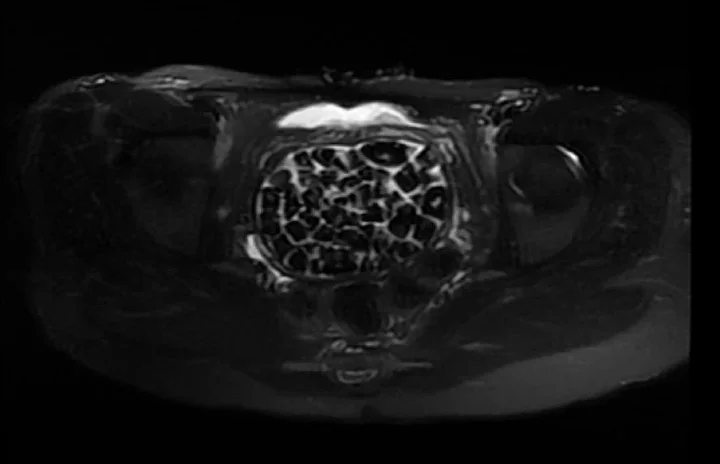

Hastasının durumuna yönelik konuşan Üroloji Uzmanı Doç. Dr. Erkan Erkan, "Hastamızın 2004 yılında doğduğunu ardından doğar doğmaz ekstrofi vezika dediğimiz 50 binde bir görülen bir anomaliden dolayı art arda ameliyatlar geçirdiğini öğrendik. 10 yaşında yine bir ameliyat geçirmişti, gerekli görüntüleme ve tetkiklerimizi yaptırdık. Normalde mesanesinin olması gereken yerin hemen arka kısmında taşlarla dolu bir kese olduğunu gördük, bunun üzerine ek görüntülemeler; MR çektirdik. Hastamız çelişkili açıklamalar almıştı, kendi radyolojik kliniğimiz ve edindiğimiz konsültasyonlarda taşların mesanede değil vajinal boşlukta oluştuğunu düşündük, bir planlama yaptık.

Kadın doğum hocamızın da çabasıyla taşları tamamen temizledik ardından ileride normal bir hayat sürmesi bakımından oraya plastik cerrahi yaptık. 287 adet taş çıkardık, pratikte gerçekten görünce çok şaşırdık çünkü bu aynı zamanda literatürde çok nadir görülen bir olay. Biz ameliyata hazırlanırken de teorik olarak biraz araştırdık. Literatürde gördüğümüz kadarıyla buna benzer bu tanıma uyan bir vaka vardı. Literatürde sanırım yayınlanmış 2’nci vaka olacak. Farkındalık çok önemli, bilinçli bir hastamız vardı. Doğumsal anomaliyle doğan çocuklarımızda ileride bunlara bağlı bazı sıkıntılar çıkabileceğinin öngörülmesi lazım. İlgili tedavilerini alsalar bile düzenli takiplere gelmeleri gerekiyor. İleride eğer dikkat etmezse ki zannetmiyorum, tekrarlayabilir. Bu rahatsızlık ekstrofi vezikal epispadias durumu çok nadir bir durum" dedi.

Genç kızın uzun süredir devam eden karın ağrısı olduğunu söyleyerek sözlerine başlayan Jinekolojik Onkoloji Uzmanı Op. Dr. Emin Erhan Dönmez, "Mesane taşları olduğu düşünülerek daha büyük bir hastaneye refere edilmiş. Aramızda mini bir konsey yaparak muayene ettik. Vajen bir hazne görevi görerek orada durağan bir idrar, uzun süre beklediği için idrar içindeki minerallerde çökerek taşlar oluşmuş. Mesanedeki idrarın vajene akmış olabileceği ve vajende göllenen idrar nedeniyle taşların burada oluşacağını düşündük, ameliyatımızı planladık. Ameliyata tanı amaçlı girmiştik, sistoskopi (Mesane gibi idrar yollarını kapsayan kısımlardaki rahatsızlıkların teşhis ve tedavisinde kullanılan endoskopik bir yöntem) dediğimiz ameliyatı Erkan Hocam ile birlikte gerçekleştirdik.

Önce mesaneyi bir görüntüledik, mesane tabanına yaklaşık 2-3 cm’lik bir alandan vajene fistülize olduğunu gördük. Mesaneden vajene geçtiğimiz esnada tüm vajenin taşlarla dolu olduğunu gördük. Tanı amacıyla girdiğimiz ameliyatta her şey de olağan gittiği için tedaviye geçtik. Taşların çıkabileceği kadar bir genişlik sağladık. Daha sonra yaklaşık en büyüğü 2,5 cm boyutlarında olan, irili ufaklı 287 tane taşı ameliyat esnasında çıkarmış olduk. Taşların tekrarlamaması için idrarın göllenmemesi, en azından dışarıya rahatça boşalabilmesi için vajinal rekonstrüksiyonu sağladık. Ameliyatta da herhangi bir problem yaşamadık. Literatürü Erkan Hocam ile birlikte değerlendirmiştik. Primer olarak vajende birikmiş olan bu kadar çok sayıda taşla ilgili bir makale görmedik, rastlamadık" dedi.